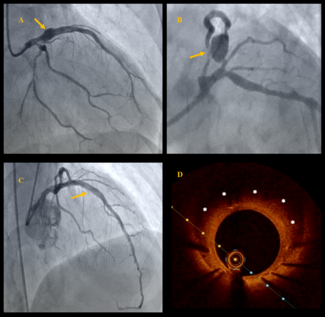

A 72-year-old woman with diabetic nephropathy was admitted for non-ST segment elevation myocardial infarction. She had undergone percutaneous coronary intervention to the ostial left anterior descending and left circumflex arteries 2 years...

An 80-year-old man with a history of acute inferior myocardial infarction was admitted to our hospital. He had undergone bare-metal stent (3.5/28 mm) implantation in the mid-right coronary artery 22 years prior.